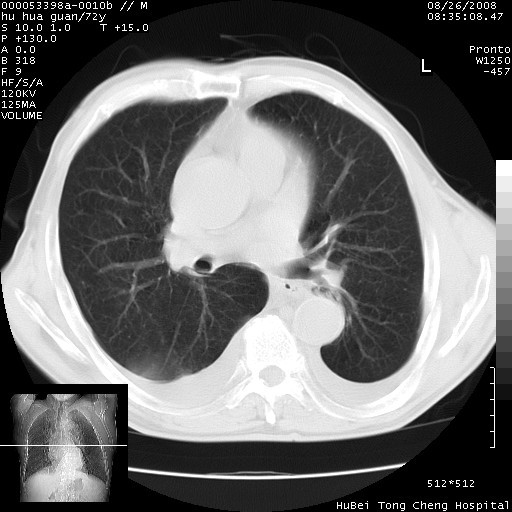

标题: CT15582:M,72Y。请老师帮分析胸部病变。

可以明确的说。肯定不是主动脉夹层破裂出血!考虑为淋巴瘤或间叶组织来源的恶性肿瘤可能性大。右肺小结节建议薄层观察,如能发现恶性征象,那椎前改变就考虑为转移所致。至于双侧少量胸水乃静脉血回流受阻所致。

图像及窗宽窗位均不理想。周围性肺癌/胸腔积液/纵隔积液。

1、右肺周围性肺癌、胸腔积液(双)

1、右上肺结节病变,肺泡癌不除外,请随诊;左下肺近后纵隔病变,考虑纵隔型肺癌侵犯大血管可能;

2、右下肺背段少许炎症,双侧胸腔积液,右下肺纤维索条。

降主动脉前移位,后纵隔占位

后纵隔占位,降主动脉前移位;双侧胸腔积液;应排外食管病变侵犯血管可能;